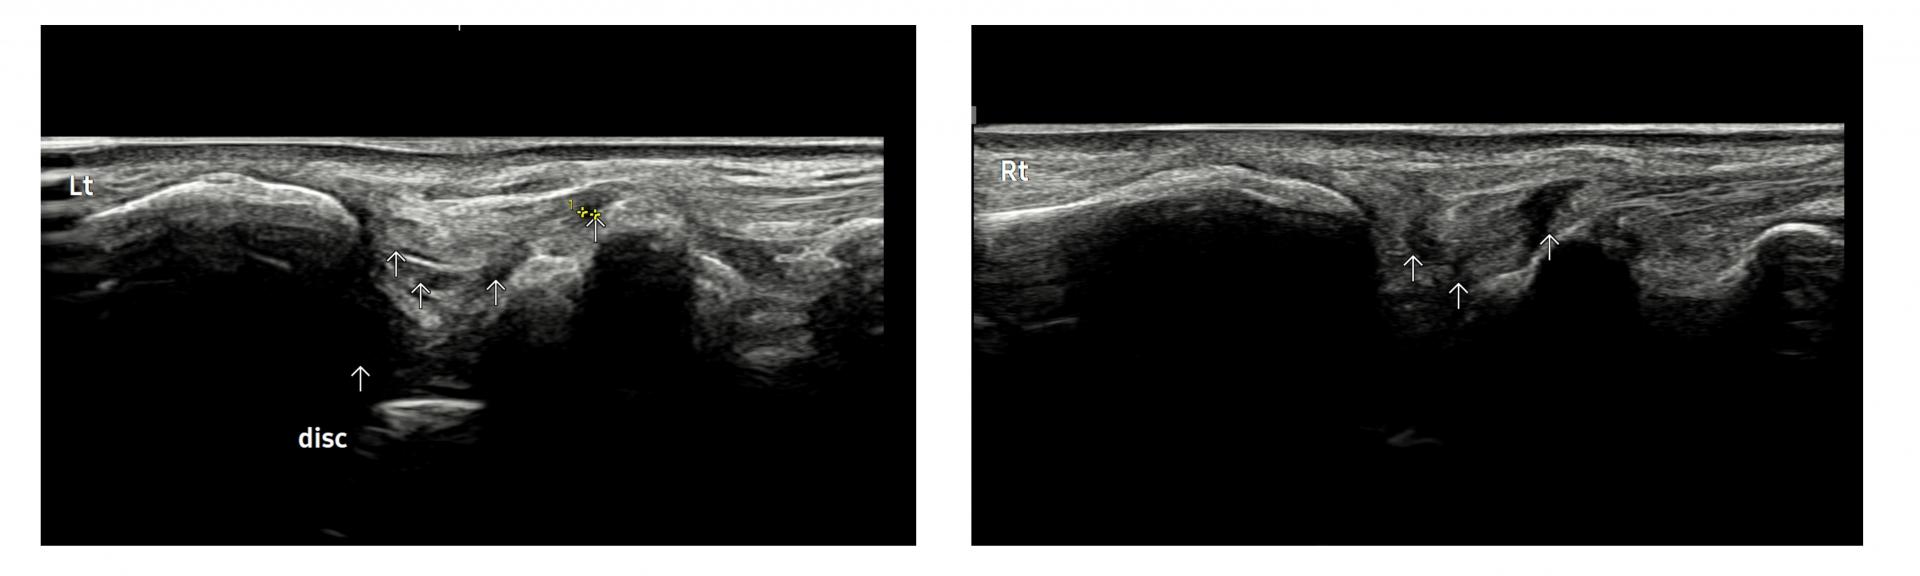

- 치료기간 : 2025. 5. 1. ~ 2025. 6. 14

- 치료횟수 : 10 회

[치료 전]

[치료 후]